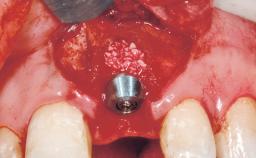

A 39-year-old male patient presented with a chief complaint of discomfort and gingival discoloration around his maxillary left central incisor. He was in good general health and was a non-smoker. His past dental history was significant because of the traumatic fracture of tooth 21 in a sporting accident at age 13. Initial dental treatment included endodontic therapy and a full-coverage restoration. The patient became symptomatic 5 years later, when structural failure of the tooth resulted in the dislodgment of the crown. Endodontic retreatment, apical surgery, and post-and-core restoration were performed.

| # of Implants | 1 |

| Type of Implants | One-Piece |

| Attachment | One-Piece |

| Placement Protocol | Early or late implant placement |